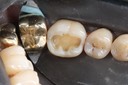

Gary Umeda #18, 19, 20 prep